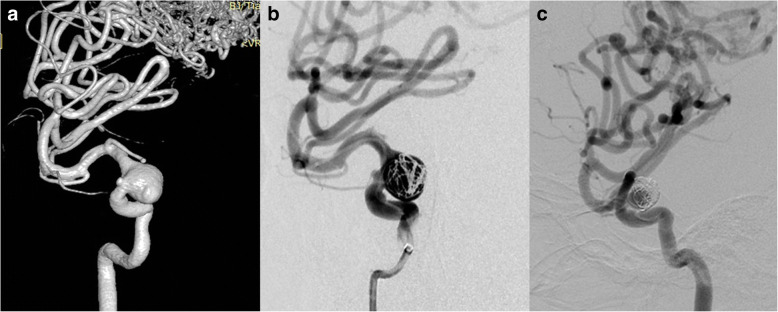

Fig. 2.

Case NO. 2 was a young female with a large cavernous aneurysm and a coexisting Spetzler-Martin grade 3 AVM of the right temporoparietal region (a). Immediate postoperative angiogram (b) and 7 months angiographic follow up (c) indicated that the size of the aneurysm has decreased but still partial embolised

Fig. 3.

Case NO. 3 was an ophthalmic aneurysm with an AVM (Spetzler-Martin 3) (a), we placed one PED (4.75 mm*18 mm) and further occluded it with 8 coils (b, c)

We have treated 3 patients (case 2, case 3, case 6) in total with an aneurysm whose parent artery was also the feeder of an ipsilateral AVM. Case 2 was a young female with a Spetzler-Martin grade 3 AVM of the right temporoparietal region. This diagnosis was confirmed 14 years ago when epilepsy firstly onset. This patient was on regular image follow up, and the DSA performed 10 months ago revealed a newly formed cavernous aneurysm (Fig. 2a). Since the aneurysm is the vulnerable part for rupture, we deployed a PED of 3.75 mm*30 mm to cover the neck, then loosely coiled the dome of the aneurysm with 3 coils, namely, Presidio 10 coil 7 mm*30 cm (Codman, USA), MicroPlex 10 Helical 10 mm*30 cm and 9 mm*30 cm (Stryker, USA). The total packing volume was 2.08% (Fig. 2b). 7 months angiographic follow up (Fig. 2c) demonstrated that the size of the aneurysm has decreased but still partial embolised. Case No. 3 was a 38-year-old male admitted into our department with an AVM (Spetzler-Martin grade 3) and an ophthalmic aneurysm which ruptured 45 days ago (Fig. 3a). The aneurysm measured 5 mm in length and 6 mm in width and there existed a daughter sac which presumed to be the rupture point. We then placed one PED (4.75 mm*18 mm) and further occluded it with 8 coils (Fig. 3b, c). The packing volume reached 40%. The whole procedure completed without any technical difficulties and the patient discharged without any neurological deficits, however, the patient died 20 days thereafter due to brain hemorrhage in local hospital.